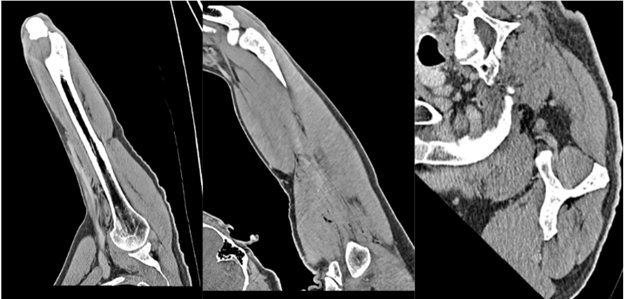

A 64-year-old right-hand-dominant male with no medical history presented with a swollen, painful right hand 10 h after a pen knife injury to the first web space. He irrigated the wound with hydrogen peroxide, but developed mild local numbness, tingling, and swelling 6 h later. He denied fever or chills. Examination revealed diffuse subcutaneous crepitus on the dorsum of the hand and forearm with intact distal sensation. Tetanus vaccination was updated. Vital signs were stable. Radiographs showed widespread SE, prompting an orthopedic consultation. The patient was admitted for observation to rule out NF. A contrast-enhanced computed tomography (CT) confirmed SE extending to the deltoid without abscess or cortical destruction (Fig. 2, 3, 4). Empiric IV antibiotics (Vancomycin, Zosyn, and Clindamycin) were initiated.

Figure 4: Computed tomography of right arm with contrast reveals no focal cortical destruction or osseous abnormality. There was mild soft tissue emphysema tracking and interspersed in the mid deltoid muscle with no drainable abscess.